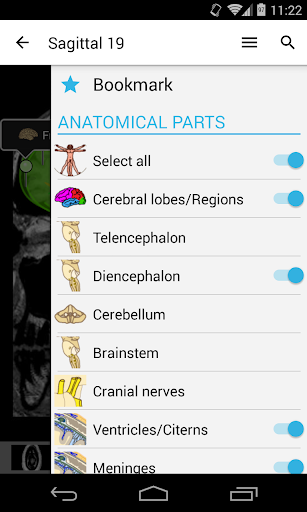

- Pilih label anatomi berdasarkan kategori

- Ganti bahasa dengan satu sentuhan tombol